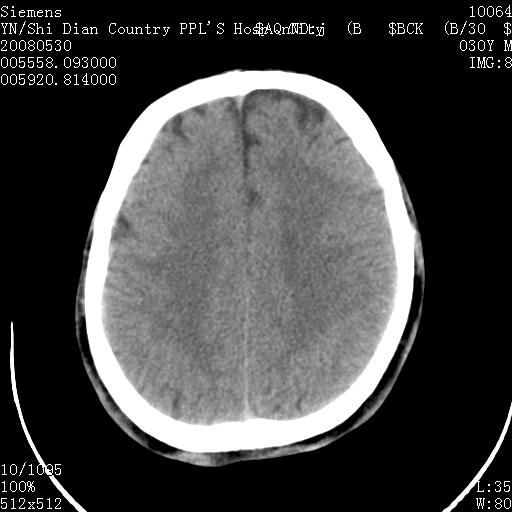

以下是引用pujunzhi在2008-7-10 13:06:00的发言:[br]透明间隔腔

以下是引用随光逐影在2008-7-10 15:19:00的发言:[br]1)考虑左侧尾状核钙化。2)透间隔间腔与vergae腔并存。

以下是引用卜一在2008-7-10 16:43:00的发言:[br]1)考虑左侧尾状核钙化。2)透间隔间腔形成。支持!